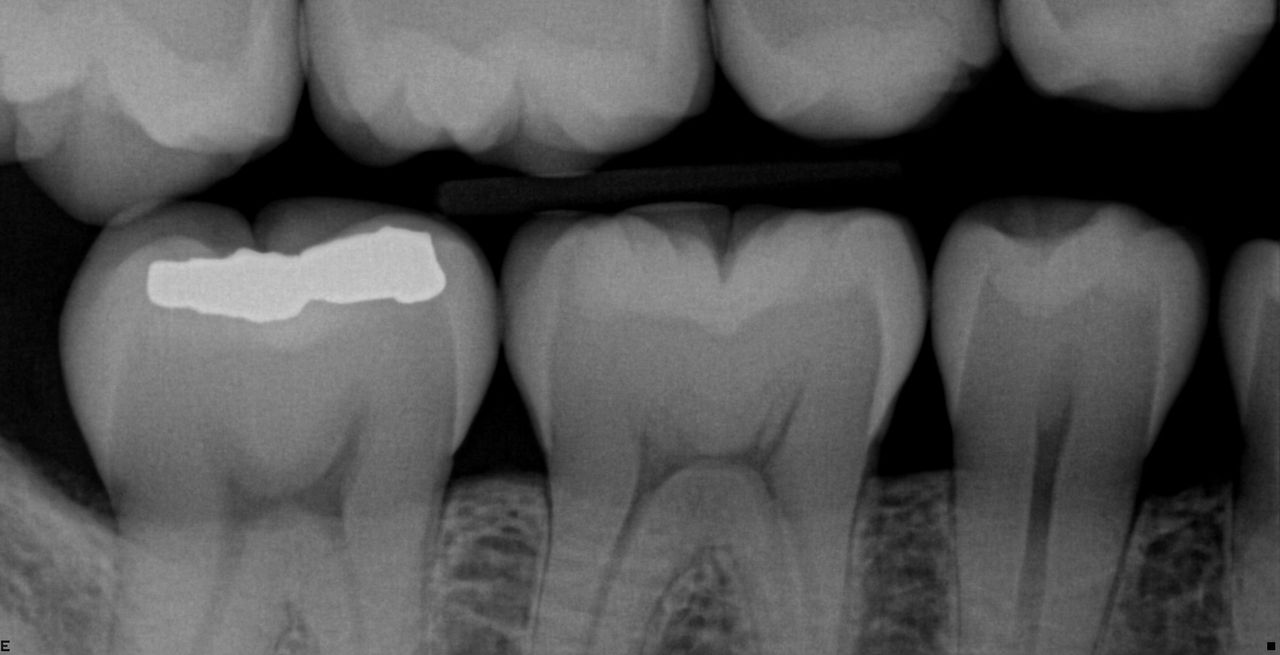

Metallartefakte sind eine Herausforderung in der 3D-Bildgebung. Röntgendichte Objekte erzeugen bei der dreidimensionalen Rekonstruktion Schatten- und Streifeneffekte, die die Befundung stören. MARS reduziert automatisch Metallartefakte und erleichtert somit die Diagnose.